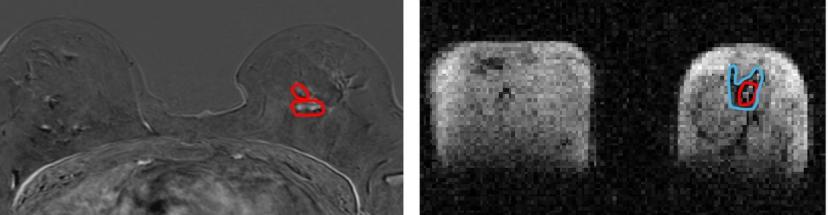

Scientists from the University, in collaboration with NHS Grampian, used a prototype version of the new Field Cycling Imager (FCI) scanner to examine the breast tissue of patients newly diagnosed with cancer. They found that the FCI scanner could distinguish tumour material from healthy tissue with more accuracy than current MRI methods.

While similar to MRI in that MRI uses strong magnetic fields and radio waves to produce detailed images of the inside of the body without touching it - the FCI scanner can vary the strength of the magnetic field during the patient’s scan. This means the FCI acts like multiple scanners in one and can extract multiple different types of information about the tissue.

Dr Lionel Broche, senior Research Fellow in Biomedical Physics and lead researcher in the study said: “We found that images generated from FCI can characterise breast tumours more accurately. This means it could improve the treatment plan for the patients by improving the accuracy of biopsy procedures by better detecting the type and location of tumours, and by reducing repeated surgery so really, the potential impact of this on patients is extraordinary.